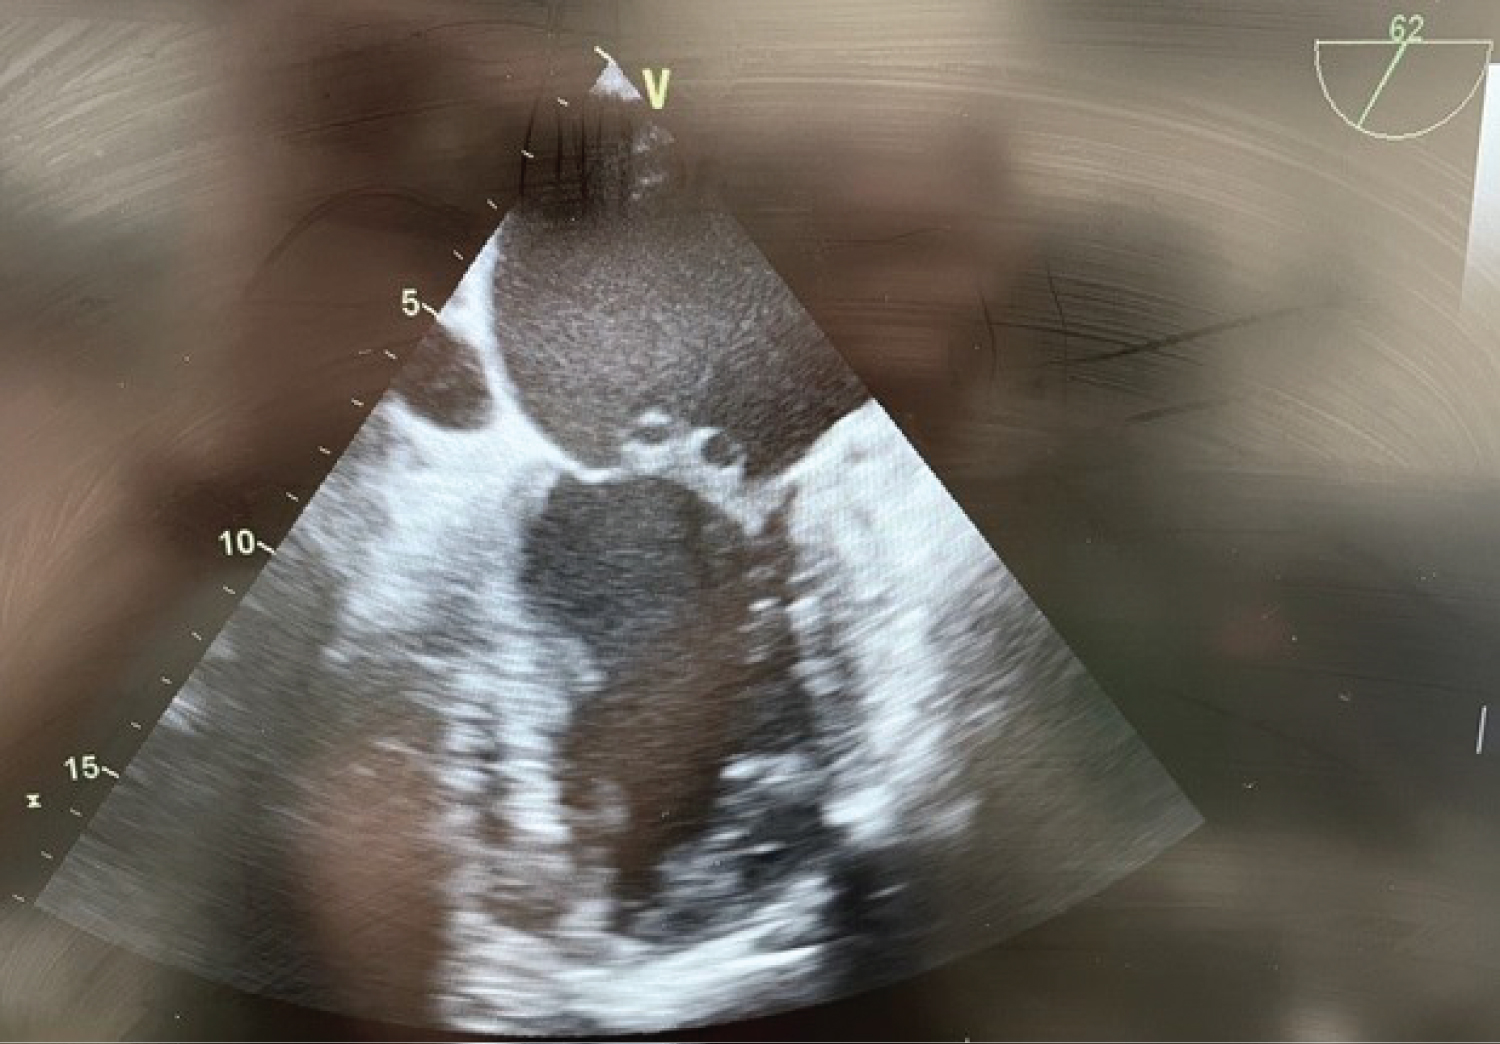

After an uneventful induction of anesthesia and placement of lines, a pre-bypass TEE confirms the presence of the A2 vegetation (Figure 1) and perforation with severe MR (Figure 2). The patient is also found to have moderate AI (Figure 3) and a patent foramen ovale (PFO) with left to right shunting (Figure 4). The surgeons are informed of the new findings and plans are made to close the PFO and to inspect the aortic valve. Aortotomy is made, and the aortic valve is found to have redundant tissue. Both the aortic and mitral valves are replaced with mechanical St. Jude's valves. The PFO is closed with a single suture, followed by de-airing of the heart under TEE guidance and weaning from CPB.

Figure 1: Pre-bypass TEE midesophageal bicaval view illustrating the PFO. View Figure 1